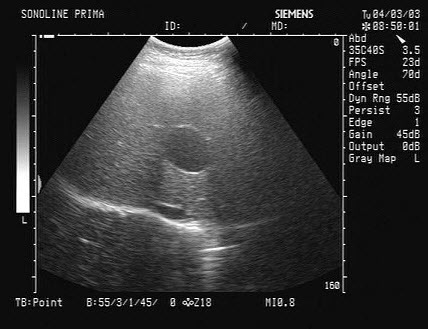

9、单项选择题

女,51岁,纳差、消瘦。结合超声声像图,诊断为()

A.胰腺癌